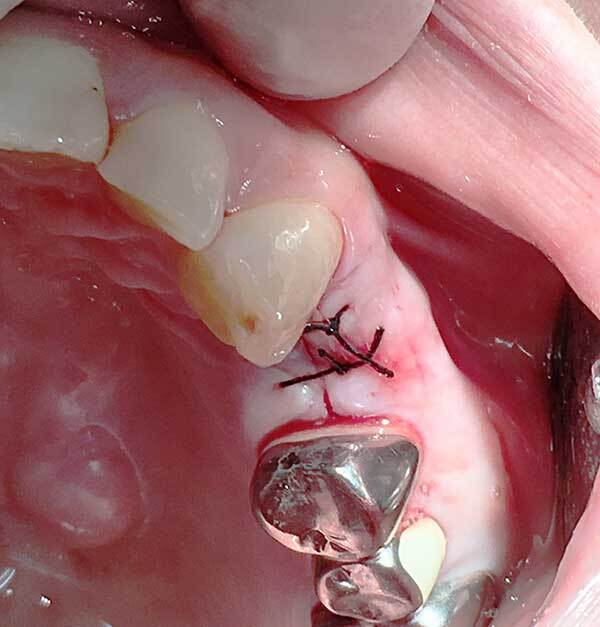

顔面外傷、歯科救急

当院唯一といってよい強みのある分野です。転倒などでの顔面、頭部外傷に関して対応可能です。頭蓋内血腫、外傷性クモ膜下出血の否定をされたうえで受診してください。脱臼歯、顔面の挫創に関しても縫合などの処置可能です。

日々、救急医として高エネルギー外傷などを対応しているため対応可能です。

また骨折などに関しては適宜入院可能な口腔外科病院に紹介いたします。

上の症例は救急受診されたお子さんの顔面外傷ですが、緊急受診し創部処置を行い即時ワイヤー固定と脱臼した歯の再植術で無事失活せず保存できました。また顔面、口腔内の外傷に関しても傷を残すことなく治癒することができました。当然全身状態、Vitalチェックを行い医科的な問題はないと考えたうえでの対応です。これは歯科医では対応不可能な部分です。救急医としての特性を生かしたものといえます。